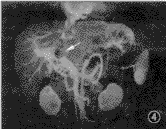

图1~4 男,41岁,肝左叶巨块型肝细胞癌,门静脉瘤栓(箭头)。图1和图2为true-FISP横断及冠状面T2.WI,门静脉呈亮信号,腔内瘤栓清晰显示;图3为TSE T2WI,门静脉瘤栓呈略高信号肿块,显示不及true-FISP;图4为对比增强门静脉MR血管造影,证实门脉瘤栓存在

true-FISP选用很短的TR和TE,流动效应几乎可以忽略不计,血液的长T2特点可以得到很好的体现[7,8]。在true-FISP T2.WI中,动脉、静脉都呈现高信号,门静脉系统及肝静脉的解剖结构和病变的侵犯都能清楚地显示,明显优于TSE序列(图1~3),这对于病变范围确定、病变分期分级及制定肝脏肿瘤的治疗方案都有着重要的指导意义,门脉系统的充分显示还有利于门脉高压及其侧支循环的评价,这是目前其他常规MRI序列无可比拟的。